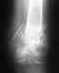

В общем, форма голеностпоного сустава правильная. Насчет самостоятельной ходьбы без костылей - это уж Вы как раз сами расскажете, когда смогли ходить без них.